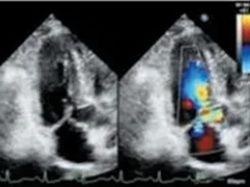

肥厚的左心室壁 二尖瓣运动曲线

左室流出道彩色血流

左室流出道血流速度